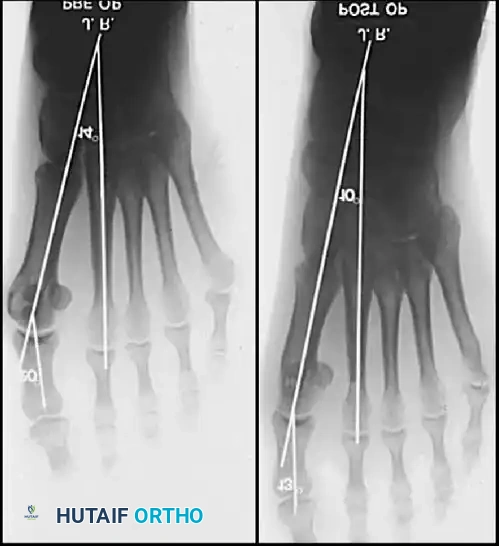

Inadequate vascularity or sensibility should be investigated thoroughly before bunion surgery is considered. In addition, the position of the articular surface of the metatarsal head in relation to the longitudinal axis of the fi rst metatarsal should be determined (Fig. 78-8). Standard preoperative radiographs should include standing dorsoplantar and lateral views, a nonstanding lateral oblique view, and axial sesamoid views (Fig. 78-9). The hallux valgus angle and the fi rst-second intermetatarsal angle should fi rst be drawn on the standing dorsoplantar view by bisecting the shafts of the bones (Fig. 78-10), with an awareness of the normal ranges. These angles are most frequently cited as guidelines for treatment decisions, but Donnelly et al. reported that interobserver measurements of the hallux valgus angle varied by approximately 6 degrees and of the intermetatarsal angle by 4 degrees. They cautioned that potential errors in measurement should be considered when these parameters are used to make treatment decisions. The hallux valgus interphalangeus angle and any evidence of degenerative arthritic changes at the fi rst metatarsophalangeal or metatarsocuneiform joints should be documented. Oddities may be present and, if overlooked, may compromise a technically well-done procedure. Mann emphasized that the presence of an os inter-

(center of the proximal diaphysis) as reference points. They found that measured correction of the hallux valgus and intermetatarsal angles varied by approximately 9 degrees depending on which reference points were used. Recommendations of Coughlin, Saltzman, and Nunley (American Orthopaedic Foot and Ankle Society Ad Hoc Committee on Angular Measurements) included standardized radiographic technique, specifi c placement of reference points (Fig. 78-11), use of a protractor rather than a goniometer for measurements, and, after distal osteotomies, dual measurements using a center-head technique and a Mose sphere.

Fig. 78-10 Method of measuring hallux valgus angle and intermetatarsal angle. Center points are connected, and intersecting lines defi ne angles.